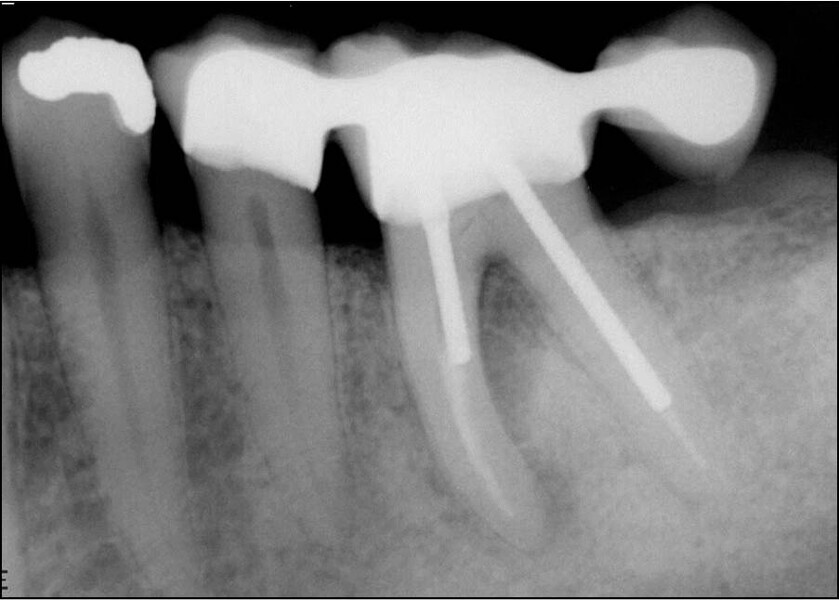

Buccal root of the bifurcated maxillary premolar—a danger zone during root canal therapy